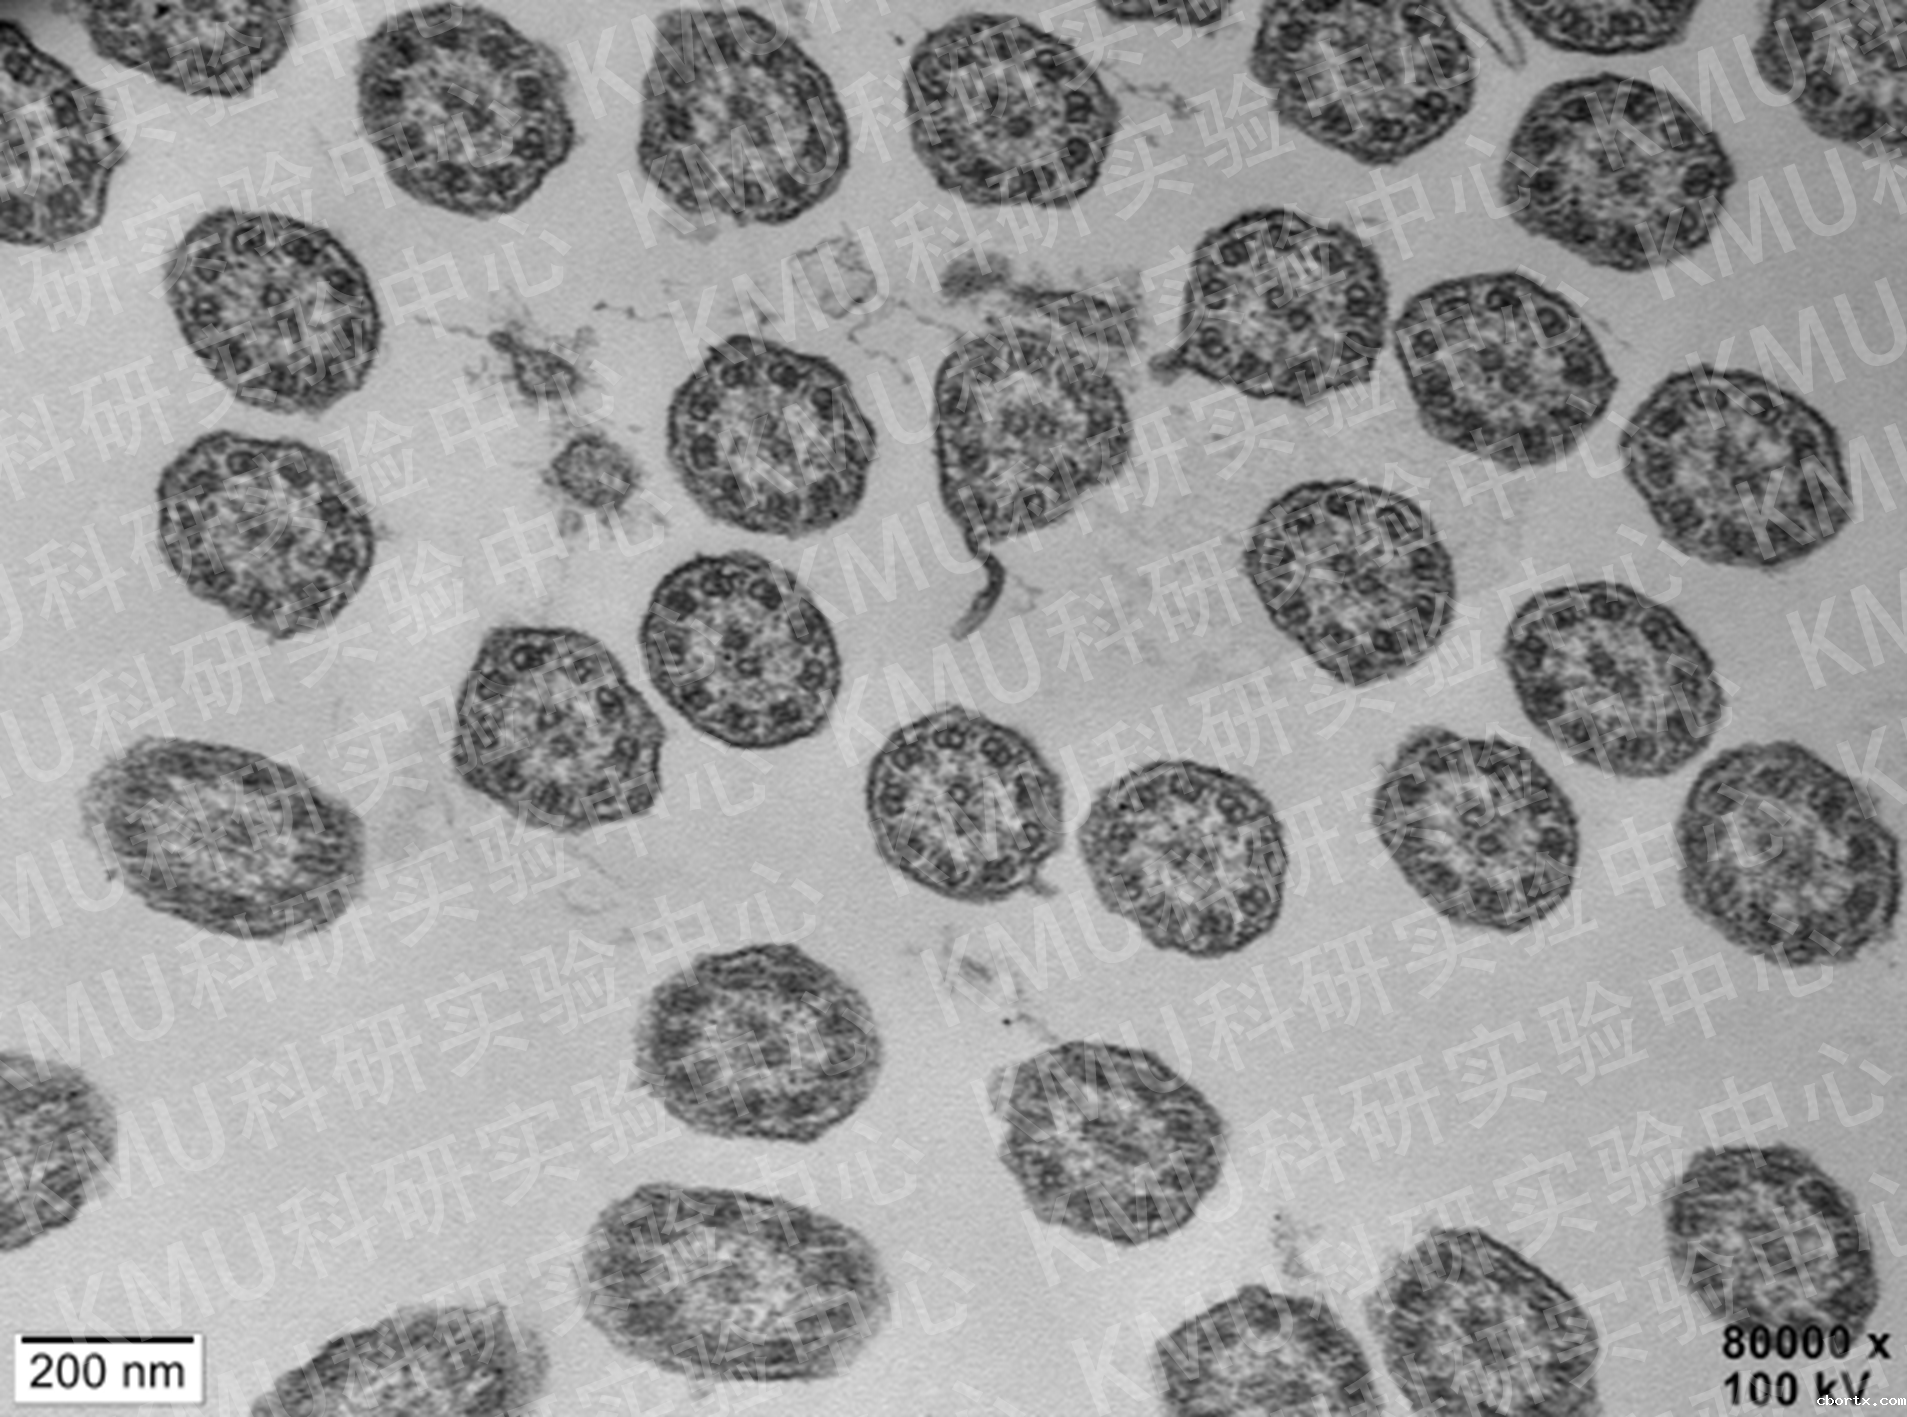

负染色技术+透射电子显微镜:

噬菌体(云南省地方病防治所 王鹏教授课题组)

培养的流感病毒